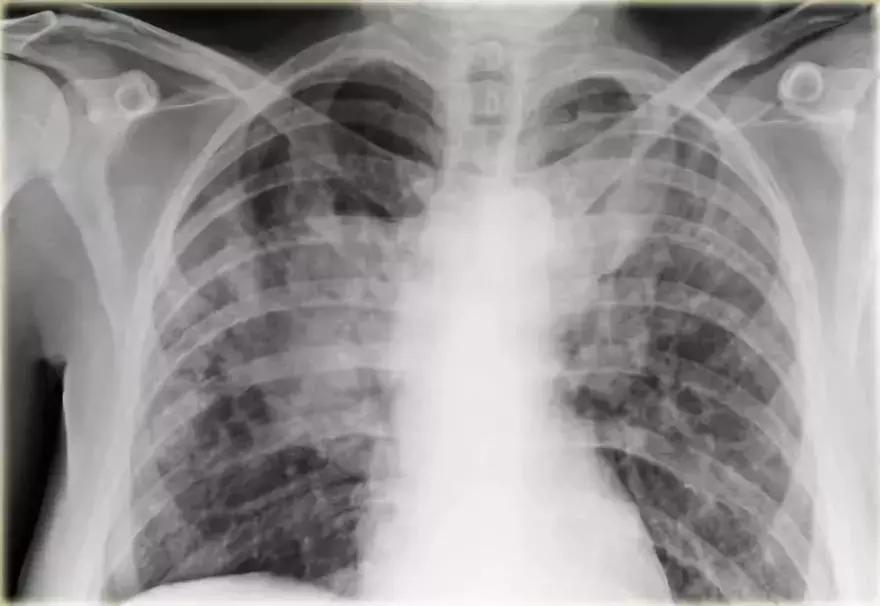

支气管肺泡癌弥漫性实变

➢ 胸部X线显示左肺出现“白肺”弥漫性实变,伴有空气-支气管征

➢ 患者是进行性实变的慢性疾病

➢ 患者左肺持续实变,最终扩散到右肺

最终诊断:支气管肺泡癌

图12 支气管肺泡癌弥漫性实变

非何杰金氏淋巴瘤

这个病例复杂,仅仅基于胸部X线不能确定是团块还是实变。CT成像对鉴别诊断帮助不大,低密度区可能是团块,也像是坏死引起的实变。基于组织活检最终诊断:非何杰金氏淋巴瘤。

图13 非何杰金氏淋巴瘤